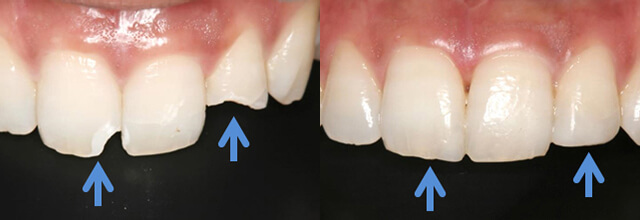

ダイレクトボンディング

削りたくない、でもきれいに治したい、そんなあなたにぴったりの方法があります。